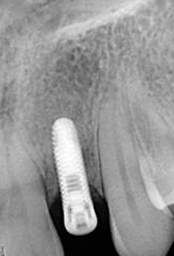

X-ray of Implant

Single Tooth Implant